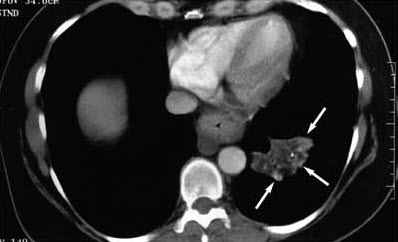

The posteroanterior chest radiograph shows an irregular spiculated mass, airspace disease, and volume loss that involves the left lower lobe with a pleural reaction. The cardiac and mediastinal configuration is unremarkable; right convex thoracic scoliosis is apparent (Figure 1). The chest CT scan (mediastinal window) shows irregular-appearing airspace disease; however, the center of the lesion has low attenuation, between 240 and 260 Hounsfield units (HU), which suggests the presence of fat (Figure 2). Bronchoscopy is nondiagnostic. A bronchogenic tumor is suspected based on the patient's history and the abnormal CT findings.

Certain radiographic findings can assist in the diagnosis of lipoid pneumonia.6-9 The most specific diagnostic finding is the quantification of the density of the consolidation via CT imaging. A negative density between 230 and 2150 HU is highly suggestive of intrapulmonary fat.9